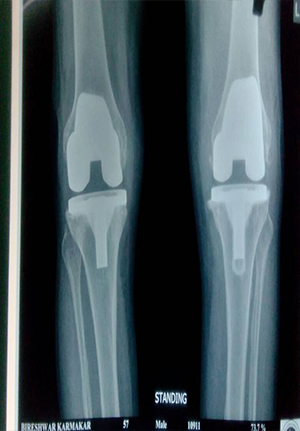

Total knee replacement in general is a very good operation for relieving pain.

Total Knee Replacement